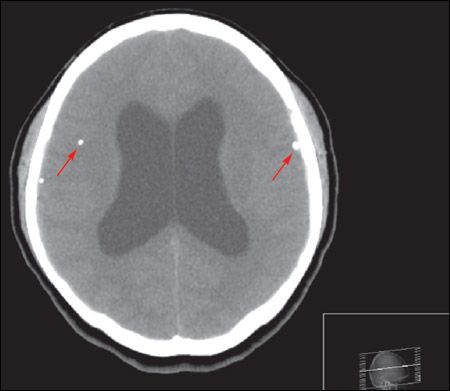

A cranial CT scan showed calcifications (arrows) scattered throughout the brain parenchyma with hydrocephalus. Intravenous ceftriaxone and metronidazole were started; phenytoin was added after seizures developed. Results from blood cultures were negative. The patient underwent a ventriculoperitoneal shunt. Results of cerebrospinal fluid analysis and culture, Cytomegalovirus serology, Toxoplasma serology, and tuberculosis polymerase chain reaction were all negative. Serology for Taenia solium was reactive. Postoperatively, albendazole (800 mg/d) and dexamethasone were started.

Neuroimaging may show a nonenhancing hypodense lesion, variable degrees of edema, calcifications, or hydrocephalus. Conditions that can present with similar features include toxoplasmosis, schistosomiasis, tuberculosis, cytomegalovirus infection, abscess, primary brain and metastatic cancers, trichinosis, and sarcoidosis. Finding a scolex as a mural nodule within the cyst is pathognomonic for neurocysticercosis. The appearance on CT or MRI scans is frequently nonspecific and may be difficult to differentiate from other brain lesions. A definitive diagnosis can be made using proposed diagnostic criteria based on clinical presentation, imaging, serology, and epidemiological data.3